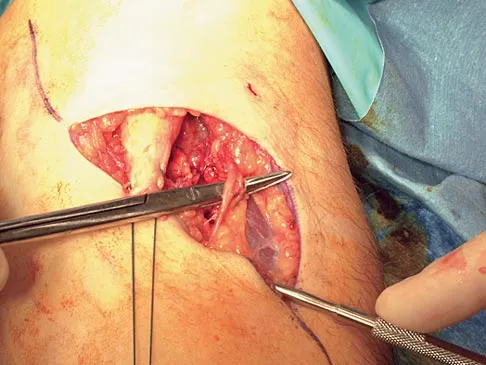

Question 59

During the anterior approach for repair of a distal biceps tendon rupture, what structure, shown under the scissors in Figure 6, is at risk for injury?

Explanation

Question 60